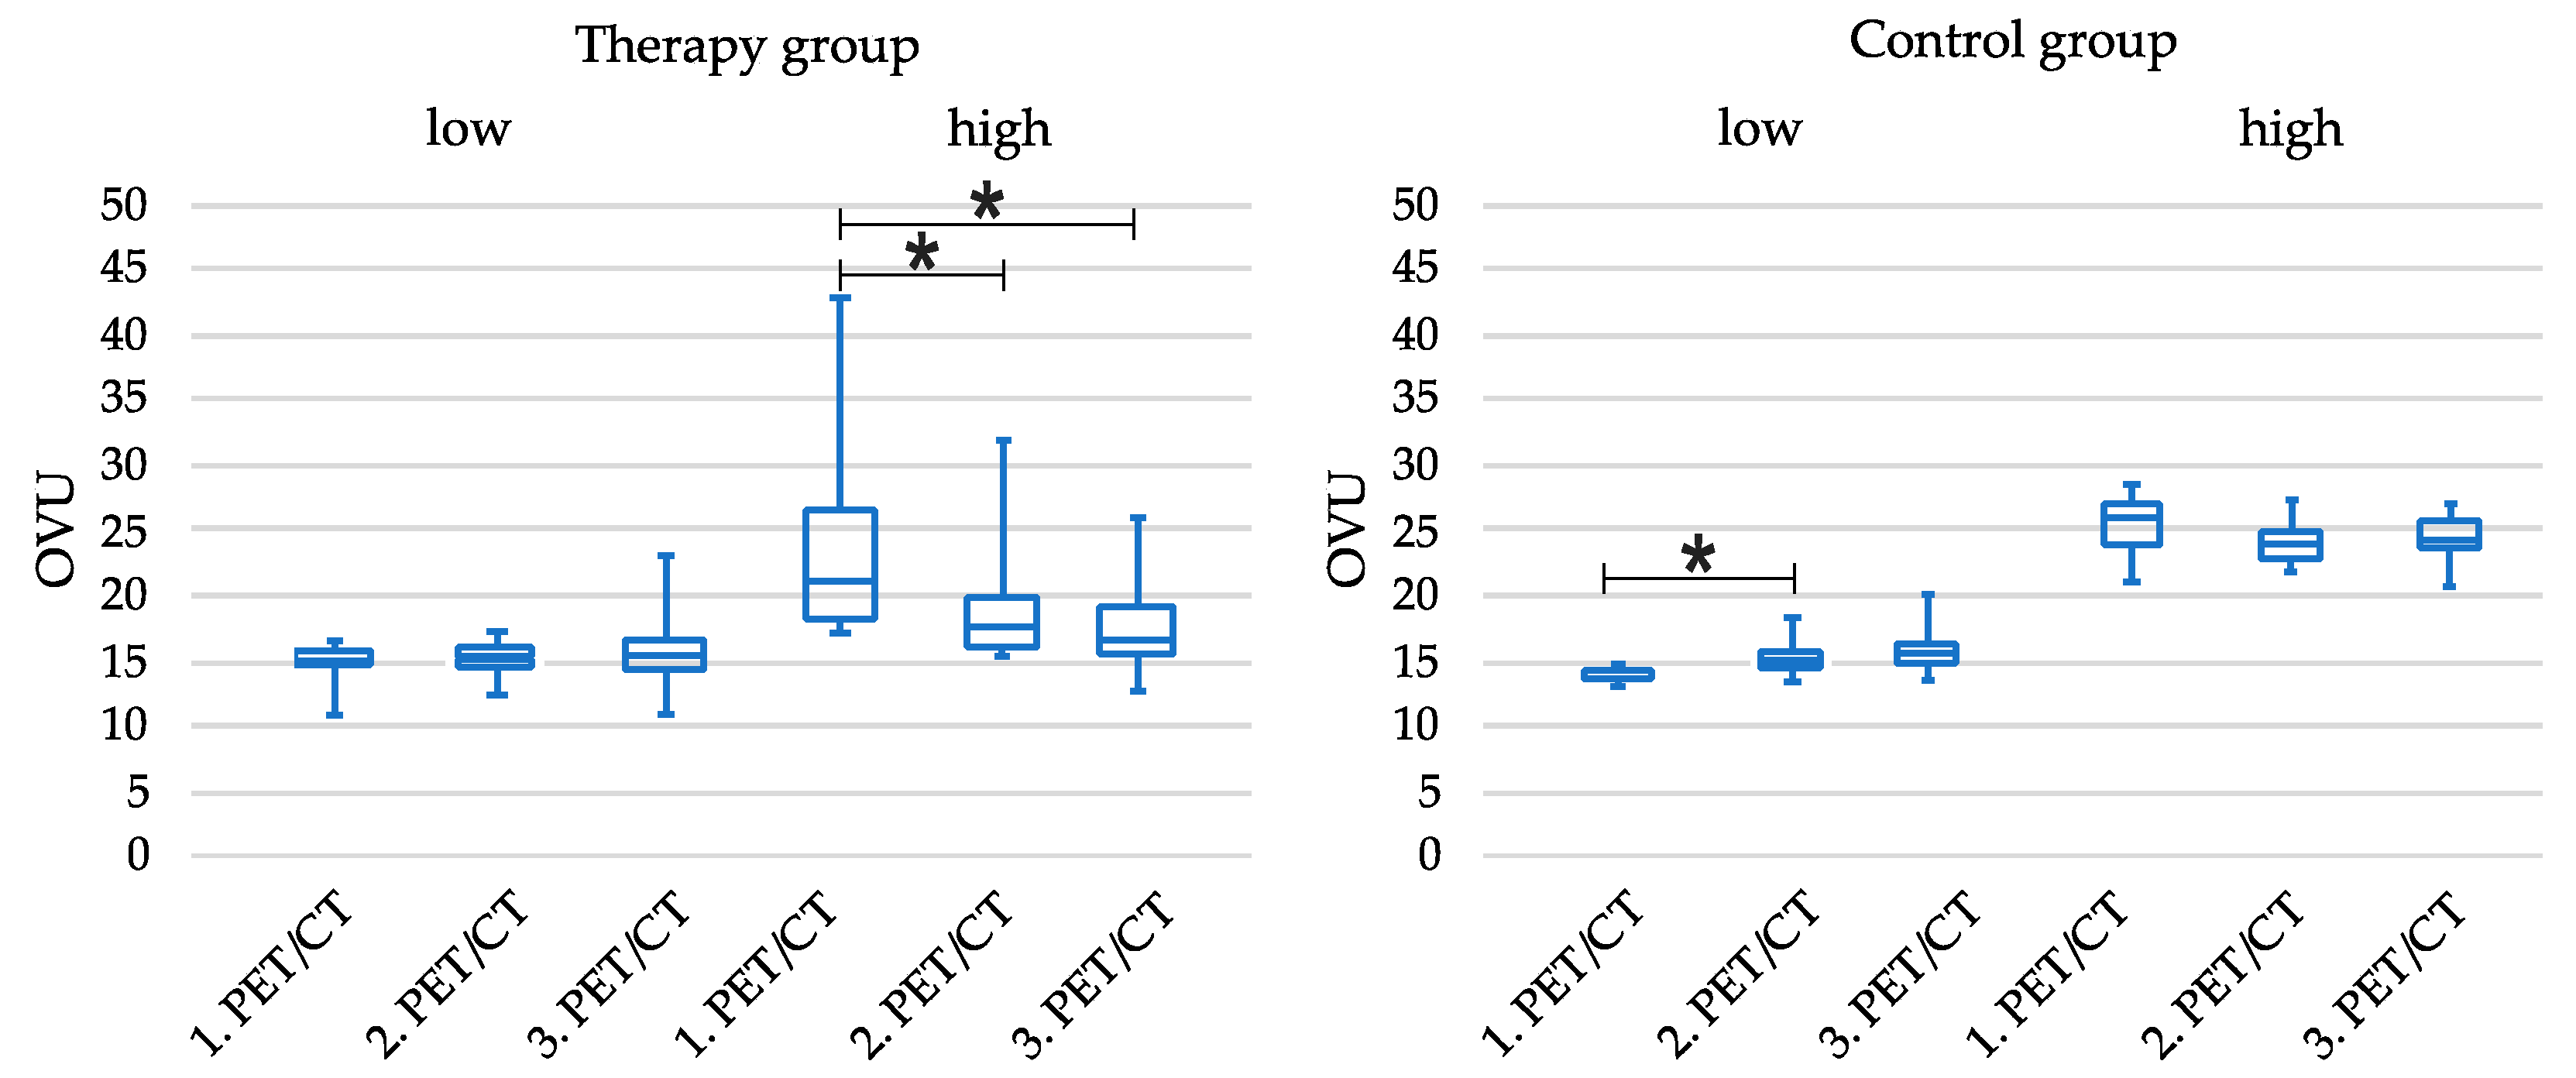

3.5. Tercile-Based Analysis of Patient Cohorts

4. Discussion